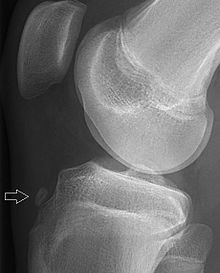

Tuberocity avulsion of the 5th metatarsal

The tuberosity avulsion fracture (also known as pseudo-Jones fracture or dancer's fracture[2] is a common fracture of the fifth metatarsal (the bone on the outside edge of the foot extending to the little toe).[3] This fracture is likely caused by the lateral band of the plantar aponeurosis (tendon).[4] Most of these fractures are treated with a hard-soled shoe or walking cast. This is needed until the pain goes away and then the patient can return to normal activities.[3] Healing is usually completed within eight weeks.[5]